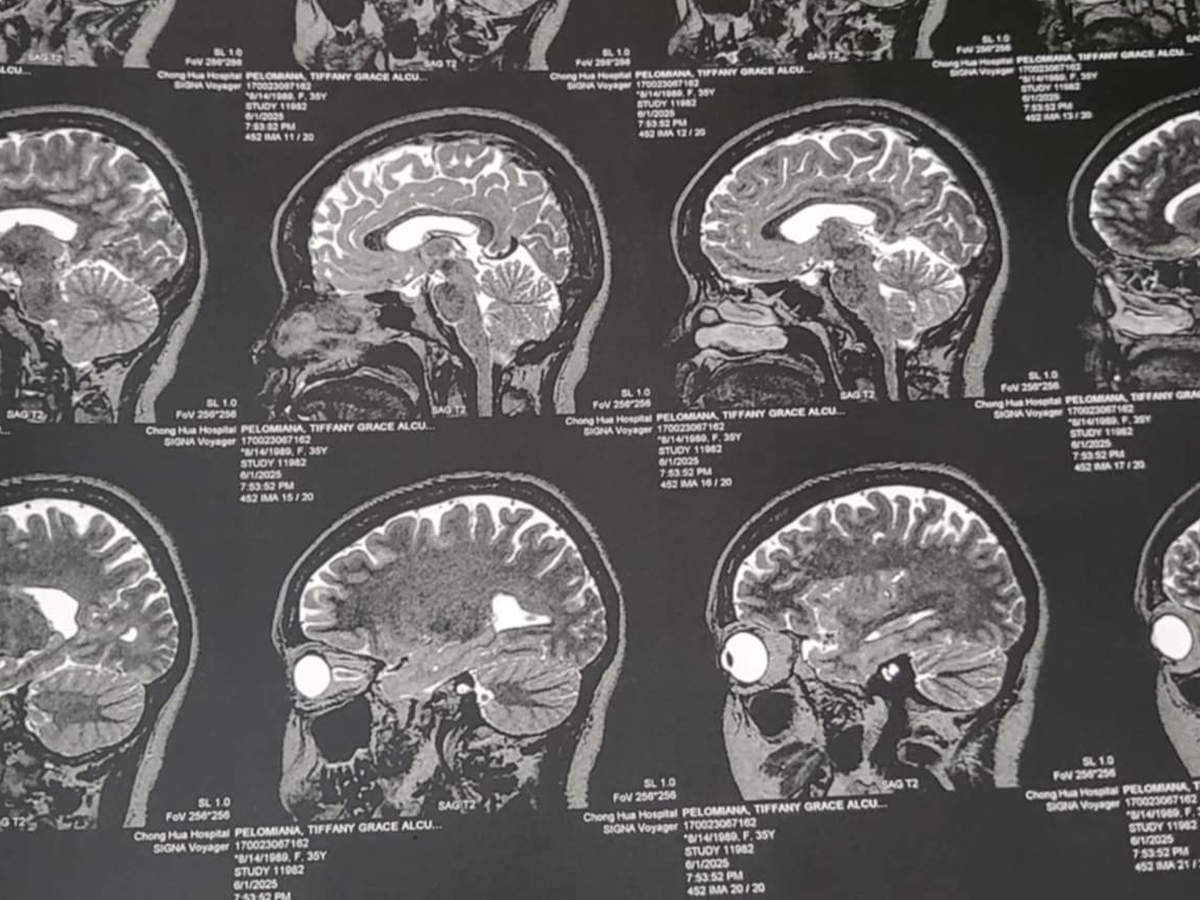

Asking for anything to help my loving sister, who is a single mother of 5. We are in the Philippines, where she can't get the treatment she deserves without the funds upfront for the surgery. She has a bleeding tumor that needs immediate surgery. This is a very difficult time, not being able to get the treatment until the surgery is paid for. Please, anything counts as time is against her.

Thank you all for your kind donations!! Sushi has been in the hospital and continues to receive medical care. The doctors have decided at this time to treat her with medication before choosing to have the brain surgery. All donations will go her hospital stay and her medications. Thank you all for your help and we pray that Sushi will recover soon!